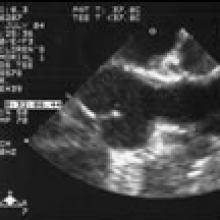

Preoperative transesophageal echocardiogram in long-axis view shows ascending aorta with aortic valve to the left. The markers indicate the aoritc root dimension to be 2.0 cm and hte mid portion of the stenosis to be 0.8 cm.